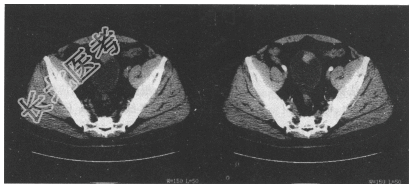

- [材料题] 患者,男,65岁。间断性血尿2个月,伴尿频、尿急1周,超声见膀胱内菜花状强回声影,尿常规红细胞(++),白细胞(+),查体未见明显异常。

- 简答题1、CT检查如下图,请问拟诊断为什么?